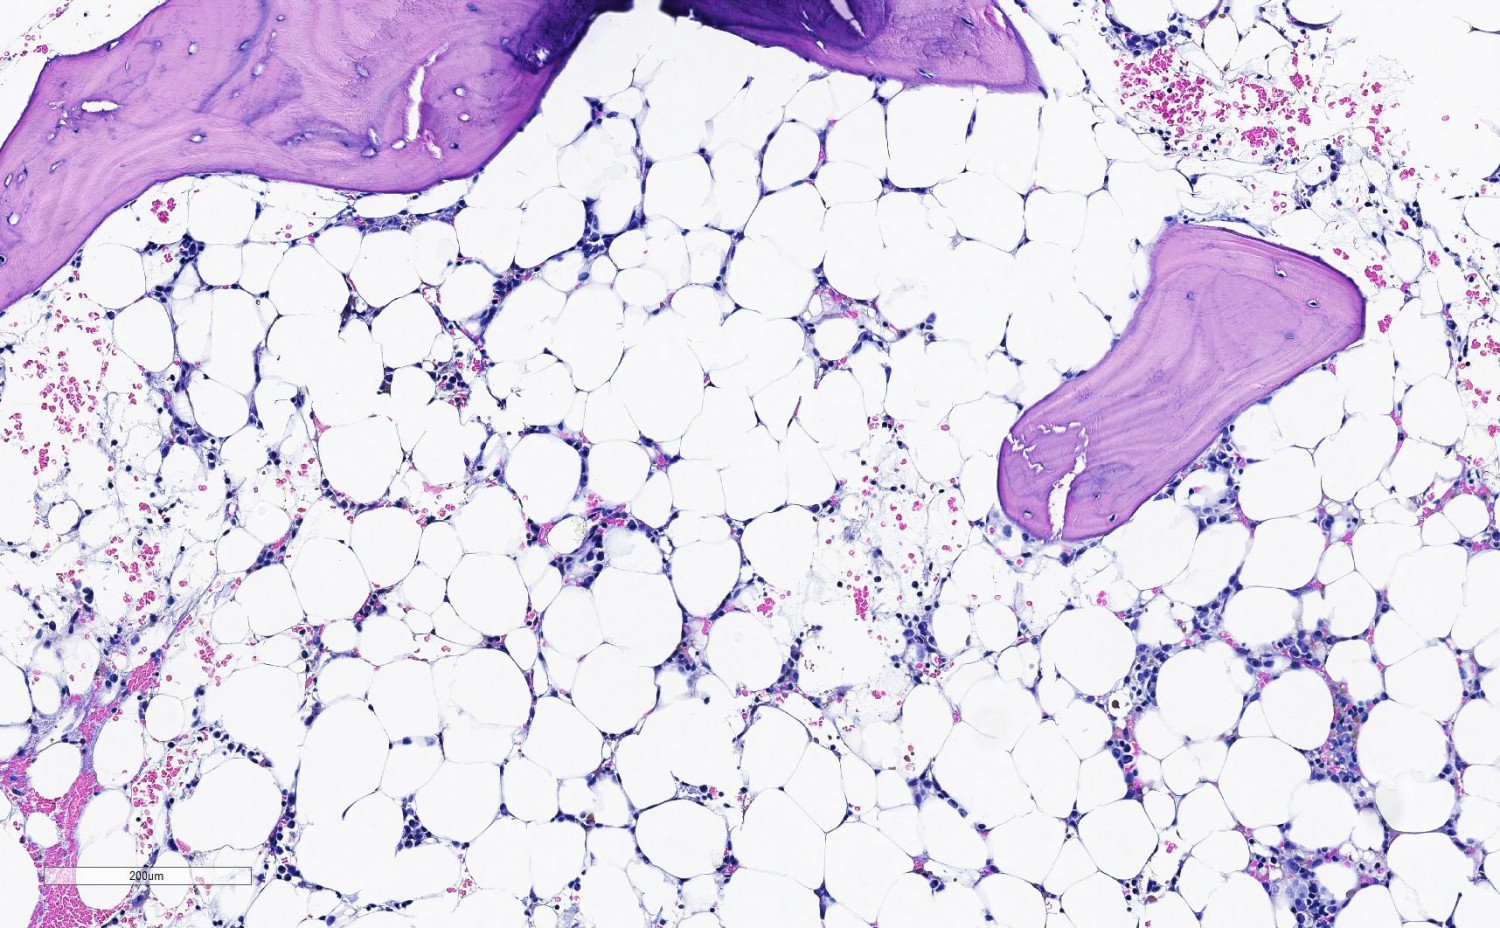

Det finnes ingen enkel test for å stille diagnosen (6). I praksis vil den først bli aktuell etter at man har tatt en benmargsbiopsi. Sammenlignet med normal benmarg (figur 1) vil man ved aplastisk anemi finne uttalt hypoplasi av hematopoese, og margrom domineres av fettceller (figur 2). I biopsien kan man samtidig vurdere om det foreligger annen primær malign benmargssykdom, lymfoproliferativ sykdom, metastaser, inflammatoriske eller infeksiøse prosesser eller tilstand med økt produksjon av blod, som ved hemolytisk anemi (figur 3).